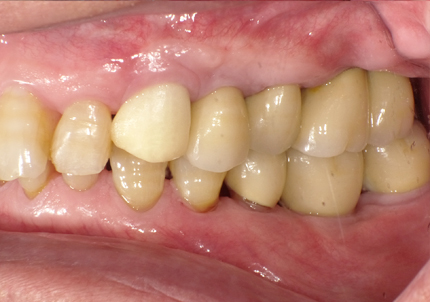

1.初診時口腔内(2007年6月30日)

↑ 2007年6月30日(初診)